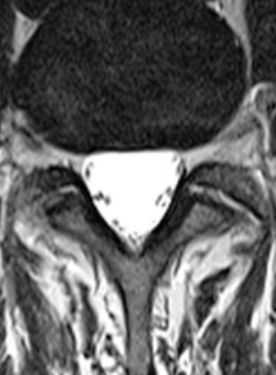

- стеноз спинномозгового канала;

Стеноз позвоночного канала поясничного отдела на снимке МРТ (Т1 взвешенное изображение)

Грыжа межпозвонкового диска и абсолютный стеноз спинномозгового канала на снимке МРТ поясничного отдела, Т2 взвешенное изображение